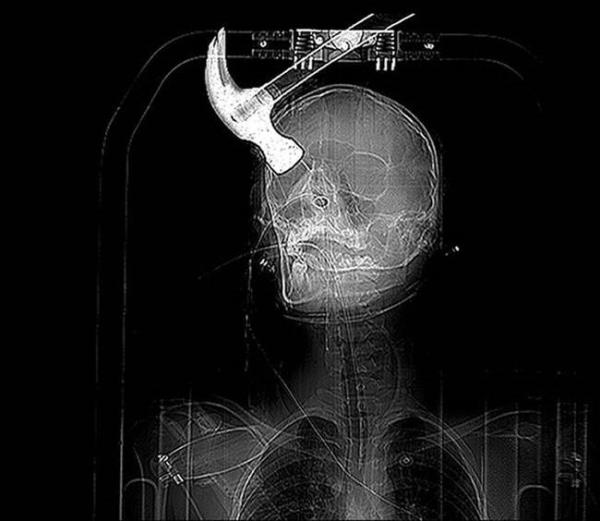

1. 18 yaşındaki Connor Huntley'nin hayatı arkadaşı Joseph Williams'ı sinirlendirmesiyle tamamen değişti. Joseph sinirlendiği Connor'ın kafasına bir çekiçle vurdu ve sonuç...

18 yaşındaki Connor Huntley'nin hayatı arkadaşı Joseph Williams'ı sinirlendirmesiyle tamamen değişti. Joseph sinirlendiği Connor'ın kafasına bir çekiçle vurdu ve sonuç...